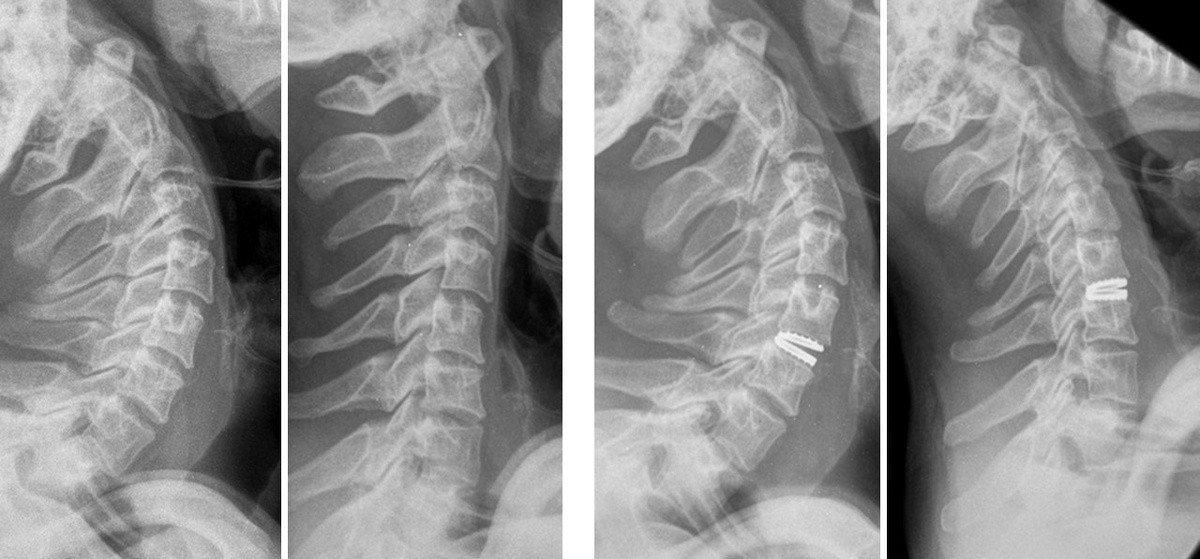

Пациент: 32 года, занимается тяжелым физическим трудом. Жалобы: более года мучили постоянные боли в шее, которые временно уменьшались только в положении лёжа. Диагностика:

Дегенеративное заболевание межпозвонкового диска с нестабильностью сегмента.

Консервативное лечение (медикаменты, блокады) не дало результата. Решение:

Эндопротезирование межпозвонкового диска — современная альтернатива спондилодезу, которая сохраняет подвижность позвоночника и снижает нагрузку на соседние сегменты. Результат:

Уже через 2 месяца после операции пациент полностью восстановился.

Вернулся к работе без ограничений. Помните: хроническая боль в шее или спине — не приговор! Современные методы лечения помогают вернуть качество жизни даже в сложных случаях.